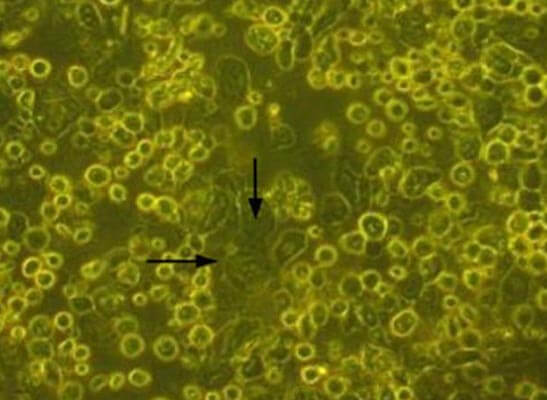

Dispase II enzyme was added to dishes containing tissue pieces & incubated at 37°C for 1 hr. Enzyme activity was then stopped by washing with DMEM containing 10% of the patient’s serum. The tissues were then treated with trypsinethylenediaminetetraacetic acid for 15 min. The cells were then cultured using a TGP-based method. Medium composed of DMEM with 10% autologous serum, insulin, penicillin-streptomycin, and amphotericin was used for culture of cells. The cells were cultured for 10–12 days. The cells proliferated and had a cobblestone appearance characteristic of epithelial cells (Fig. 1).

Figure 1: Cells in culture in the TGP-based method. The arrows indicate the cells with cobblestone morphology